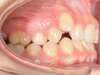

Chevauchement sévère. Traitement multibague sans extraction.

Avant